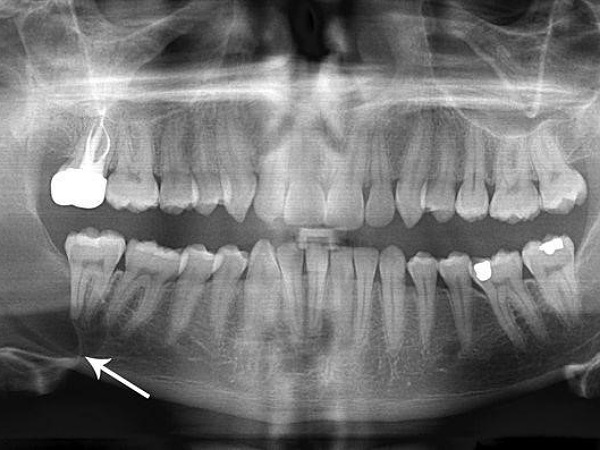

- X-ray: Taking an x-ray will help identify the abscess. It can also be used to determine whether the infection has spread, causing abscesses in other areas.

- CT scan: If the case is severe with pain, a CT scan will be recommended so as to assess the extent of the infection.